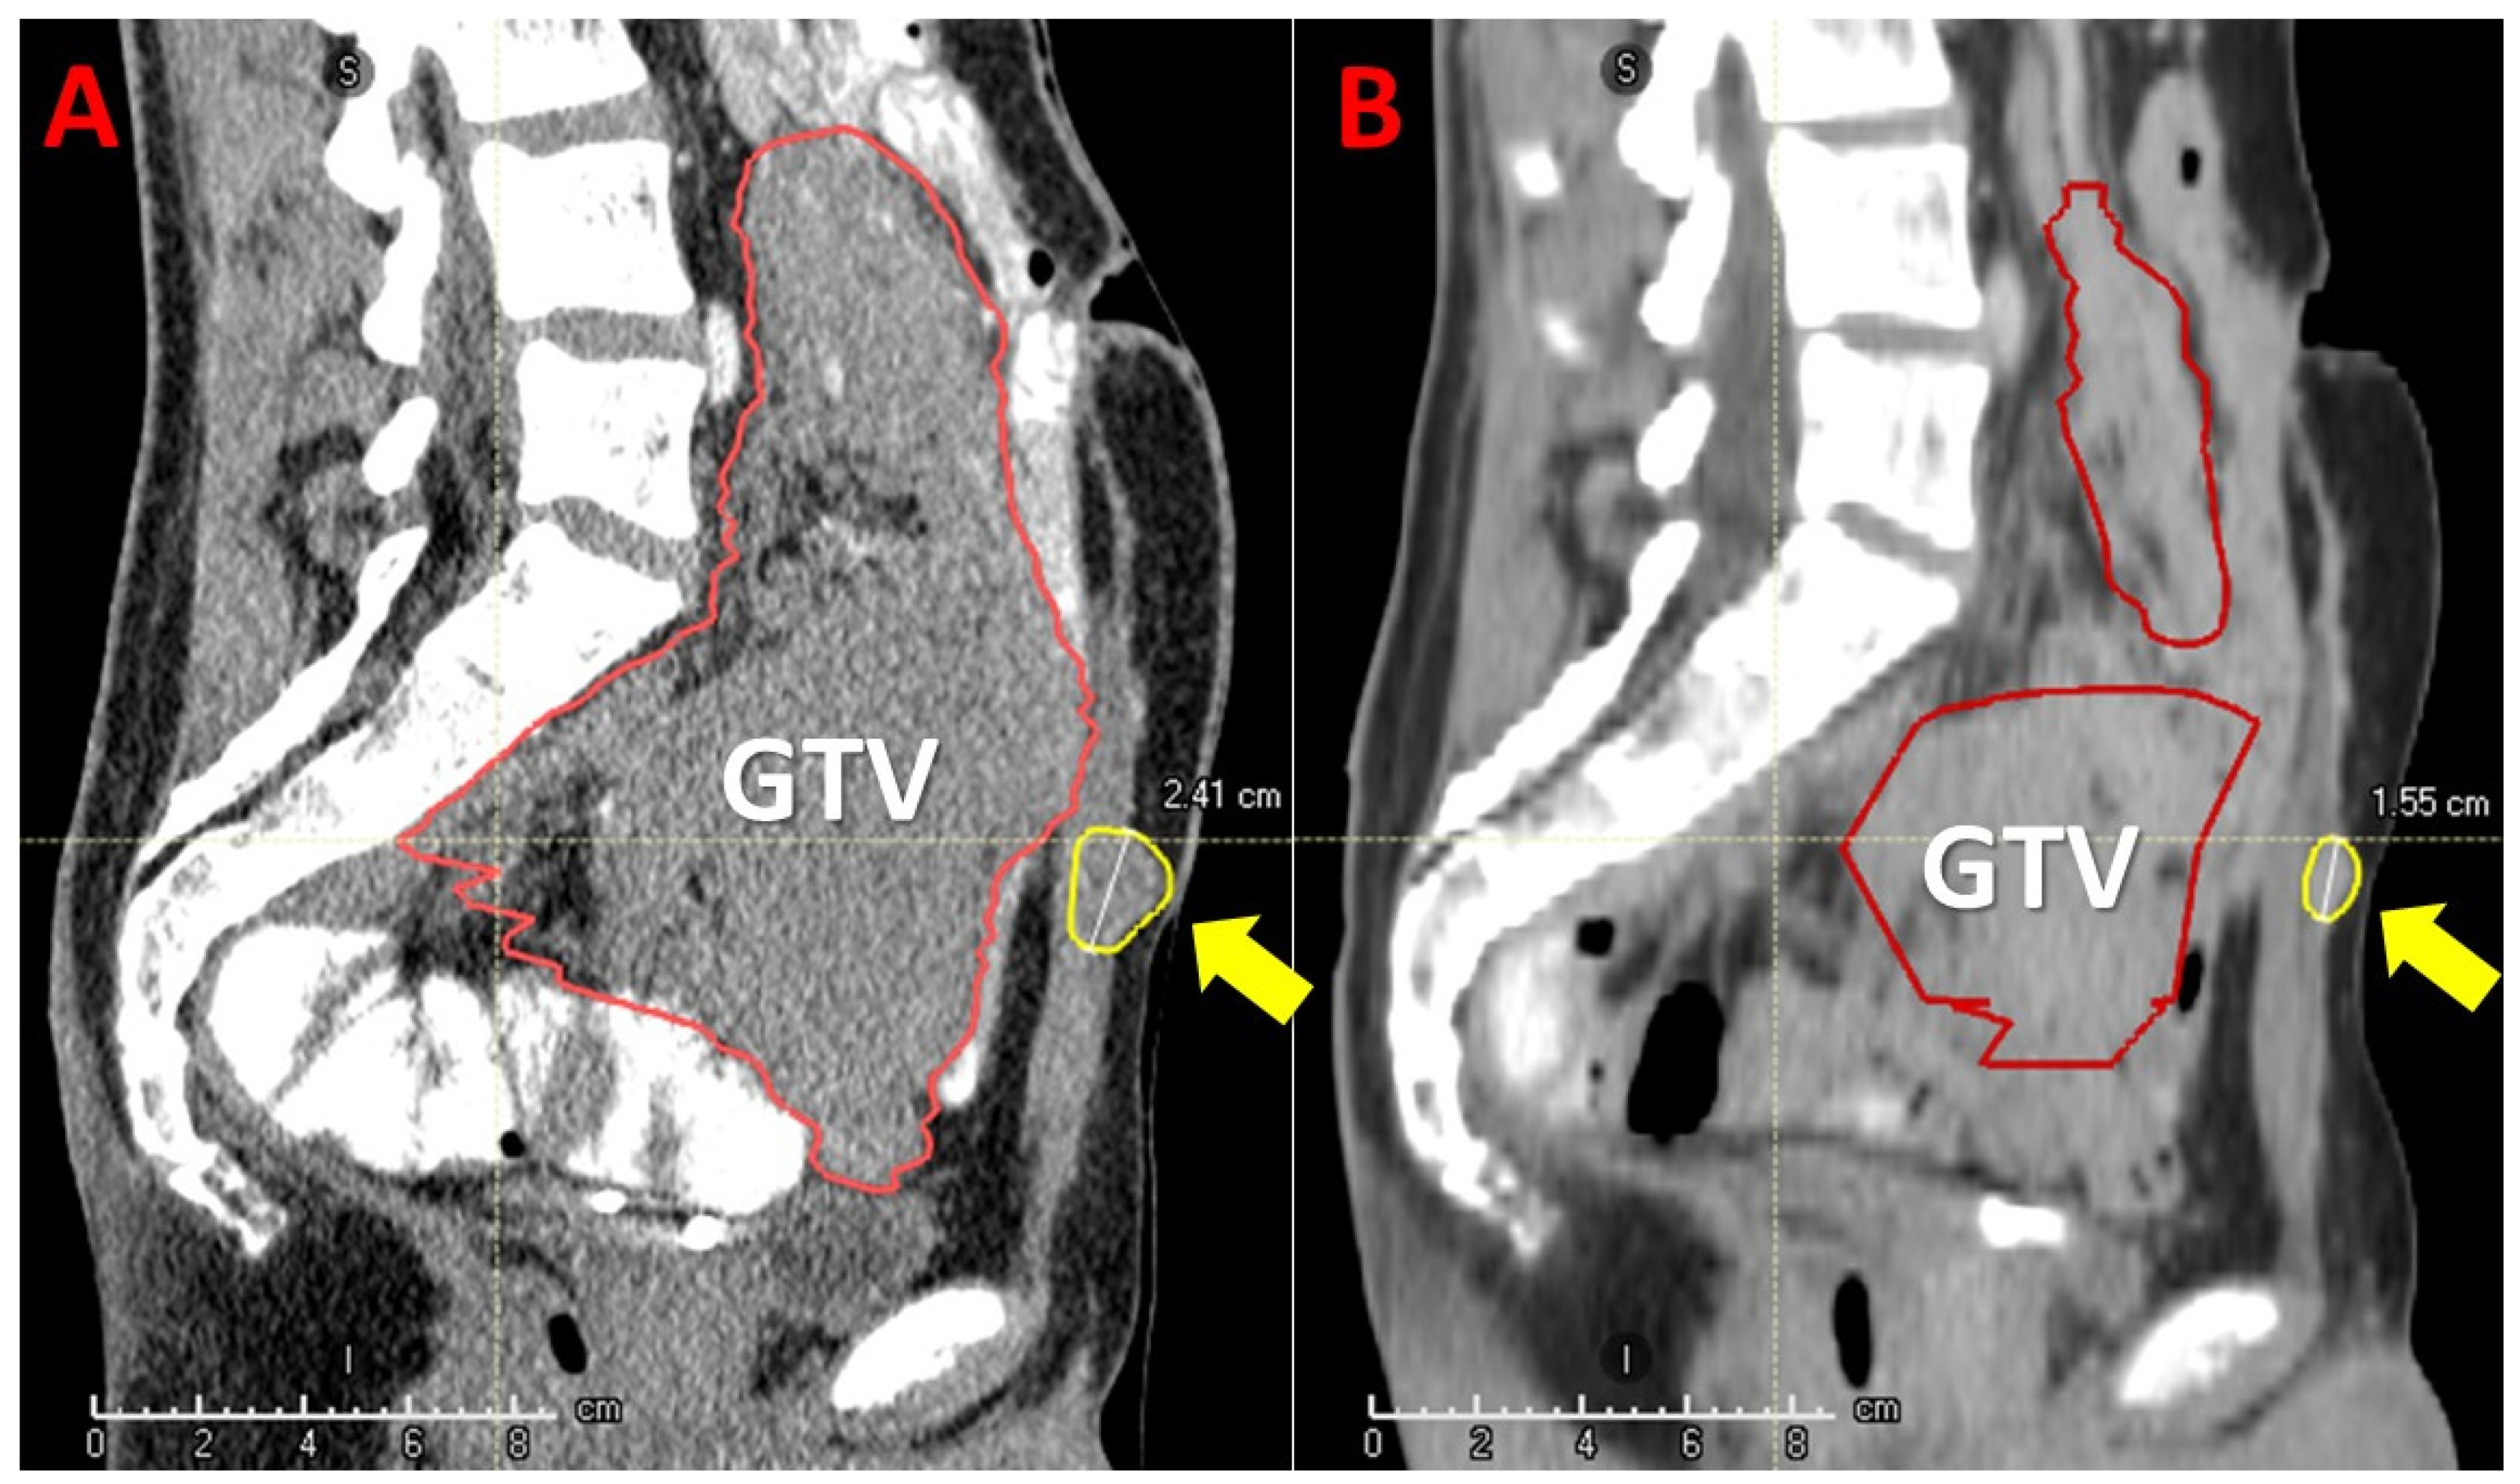

Figure 7. Bystander and abscopal effects generated by Particle-PATHY: the figure shows a significant regression of partially irradiated recurrent intraperitoneal non-seminomatous germ cell bulky tumor (yellow contour) due to the bystander effect and regression of unirradiated regional metastases (red contours) due to the abscopal effect one month following Particle-PATHY (left: before Particle-PATHY; right: after). It was not possible to offer to this 33-year-old patient any kind of conventional radiotherapy including particle therapy.